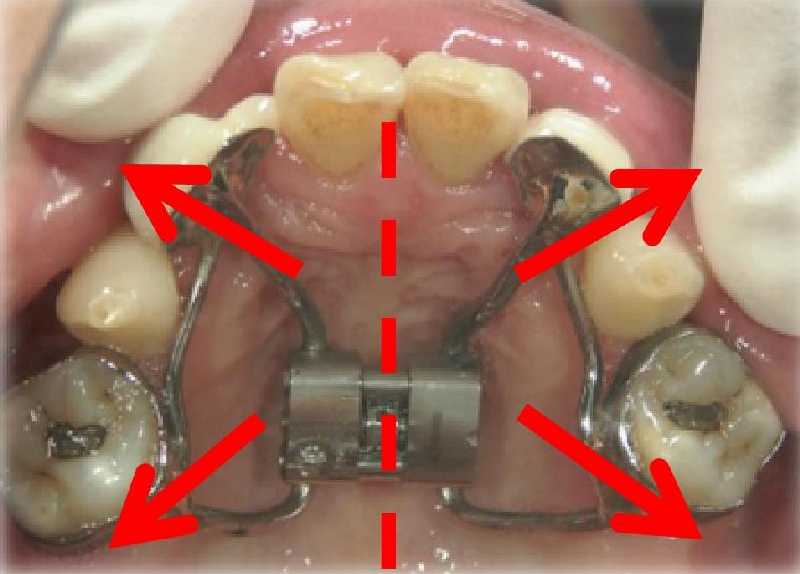

● 上顎骨の拡大

上顎(口蓋の部分)の骨に、外科手術で切れ目を入れて左右のあごのつなぎ目を切り離すことで、上顎の拡大が難しい成人の方もスムーズに広げることが可能です。